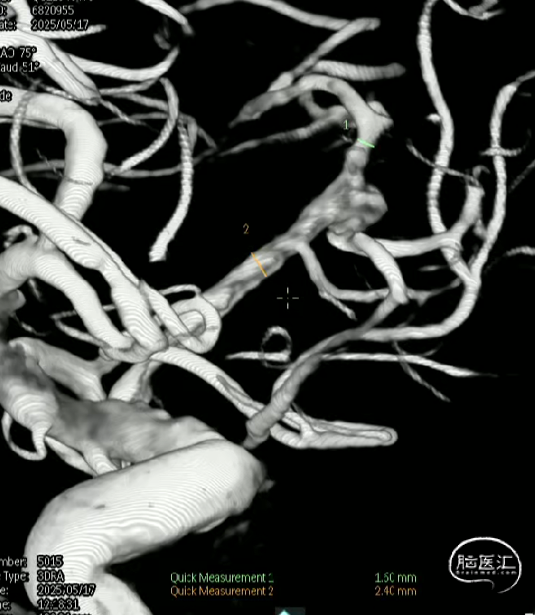

术前测量

远端锚定点:1.5mm

瘤颈远端:1.53mm

瘤颈近段:2.4mm

动脉瘤瘤体直径:4.40mm